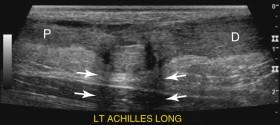

e -F igure 11-2, Full-thickness tear of the Achilles tendon. Longitudinal view shows a defect between the proximal (P) and distal (D) Achilles tendon. Refractive shadowing (arrows) is seen in the region of the torn tendon ends. Longitudinal video (see Video 11-3 ) taken while the patient flexes and extends the foot shows the change in separation of the torn tendon ends and confirms the size and location of the tear.